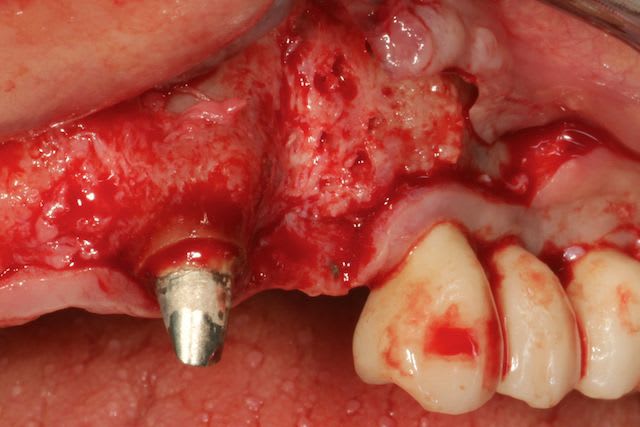

Grosse perte osseuse au niveau de la 23, ROG avec Bio-Oss et autogène dans un rapport 50/50, le tout recouvert pas une BIo-gide maintenu avec de pin's.

Désolé pour le retard, je vais essayé de répondre à tout le monde, mettre un implant et faire une ROG de façon predictible dans un cas comme ça c'est impossible, la photo pré-op c'est la dernière ( je ne sais pas pourquoi nonol m'a inversé l'ordre ), à noter que j'ai fait ce design d'incision car 24 et 25 sont des implants et je ne voulais justement pas me retrouver avec une récession.

J'ai utilisé du BIo-Oss et de l'autogène prélevé avec un scraper à la mandibule, le tout recouvert par une Bio-Gide maintenu par des pin's, suture avec du Gore Tex ( e-PTFE ) et du Cytoplast (PTFE )